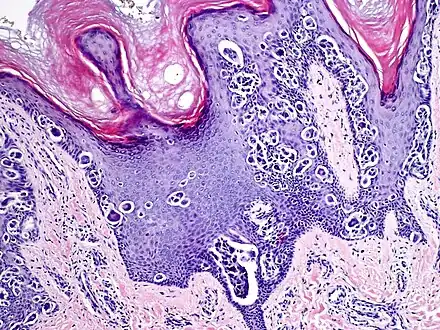

Melanocytic acral nevus with intraepidermal ascent cells (MANIAC)

An acral nevus is a cutaneous condition of the palms, soles, fingers, or toes (peripheral body parts), characterized by a skin lesion that is usually macular or only slightly elevated, and may display a uniform brown or dark brown color, often with linear striations.[1]: 1726

They are brown to dark brown in color and have linear streaks of darker pigmentation. Size is usually 7 mm or less, oval or spindle shaped, and well-demarcated. They become stable after an initial growth phase, and the number of lesions also decreases; a new lesion in middle-aged or elderly people should raise suspicion of acral lentiginous melanoma.